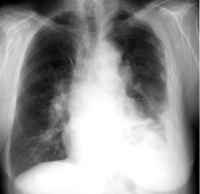

Cancer of the lung liningThe most common place for mesothelioma to develop is in the mesothelial membrane, also called the pleural lining, surrounding the lungs. About two-thirds of all mesothelioma cases develop in the pleural mesothelium or lung lining. Pleural mesothelioma is also known as cancer of the lung lining.